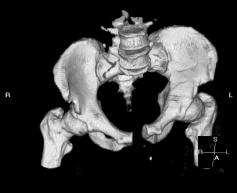

X-Rays and scans of the damaged right & left legs plus the pelvis

These x-rays were taken just after the accident. Some of the bones on the right leg have already been pushed back into the leg. The CT

scans show various views of the ankles and pelvis prior to any corrective surgery. Fibula bracing is clear in some of the images as well as

bracing that was used to secure the "open book" pelvis. In some of the last images it is apparent that the upper part of Liam’s left fibula is

broken. Liam was told that the pain he felt was most likely a muscle cramp. Nothing was done to repair this break and you will see in further

x-rays that the bone shifted and later fused in such a way as to add to the reduction of Liam’s leg length. The last photo shows the stint

used to block any potential blood clots from moving up.